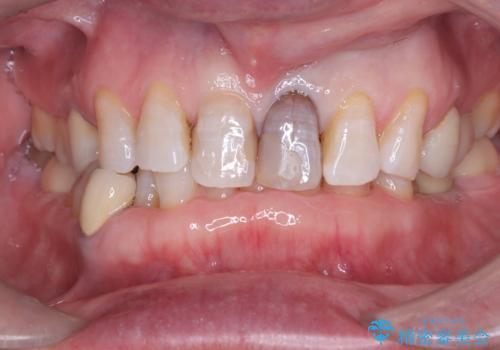

歯の変色を解消!根管治療とセラミック修復による審美的アプローチ

- 歯髄が死んで変色していた歯に対して、根管治療とオールセラミッククラウンでの修復を行いました。まず、根管治療で内部の感染を除去し、歯の強度を高めるためにファイバーコアを装着しました。その後、審美性と耐久性を考慮し、オールセラミッククラウンで覆うことで、自然な歯の色合いに近い美しい仕上がりを実現しました。

歯髄が死んだ歯は通常の健康な歯に比べて透過性が低く、特有の暗い色調を帯びる傾向にあります。変色は時間とともに進行し、薄い茶色や灰色、黄色がかった色合いになることが多いです。このような変色は、審美的な面で気になる場合が多く、オールセラミッククラウンなどでの修復が行われることも一般的です。